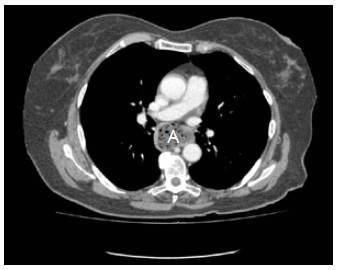

Mujer de 72 años de edad, con cuadro clínico de un año de disfagia y atragantamiento con alimentos sólidos, que había requerido tratamiento endoscópico. Se realiza endoscopia de vías digestivas altas que documenta un divertículo esofágico en tercio medio, y manometría esofágica de alta resolución, sin trastorno motor. El esofagograma (figura 1) y la tomografía computarizada de tórax (figura 2) muestran un divertículo en tercio medio de esófago, lateral derecho, de 7 cm de diámetro y base de 2.5 cm de diámetro. De manera programada se lleva a cabo diverticulectomía esofágica por toracoscopia, en decúbito prono (figura 3), sin complicaciones.

Figura 2 Divertículo esofágico de tercio medio con restos alimentarios en su interior (A).